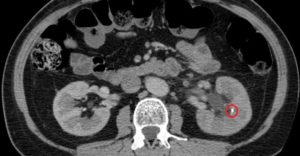

Если по каким-либо причинам камни в почках на УЗИ не удалось рассмотреть детально, особенно если они локализованы в мочеточнике, назначают КТ или МРТ почек.

Во время диагностирования на мониторе видно изображение органа в формате 3D, благодаря чему врач видит любые патологические изменения.

Зачастую МРТ или КТ почек назначают перед операцией, когда важно определить размер конкремента, его место расположения и состав. Мелкие камни на МРТ не визуализируются.